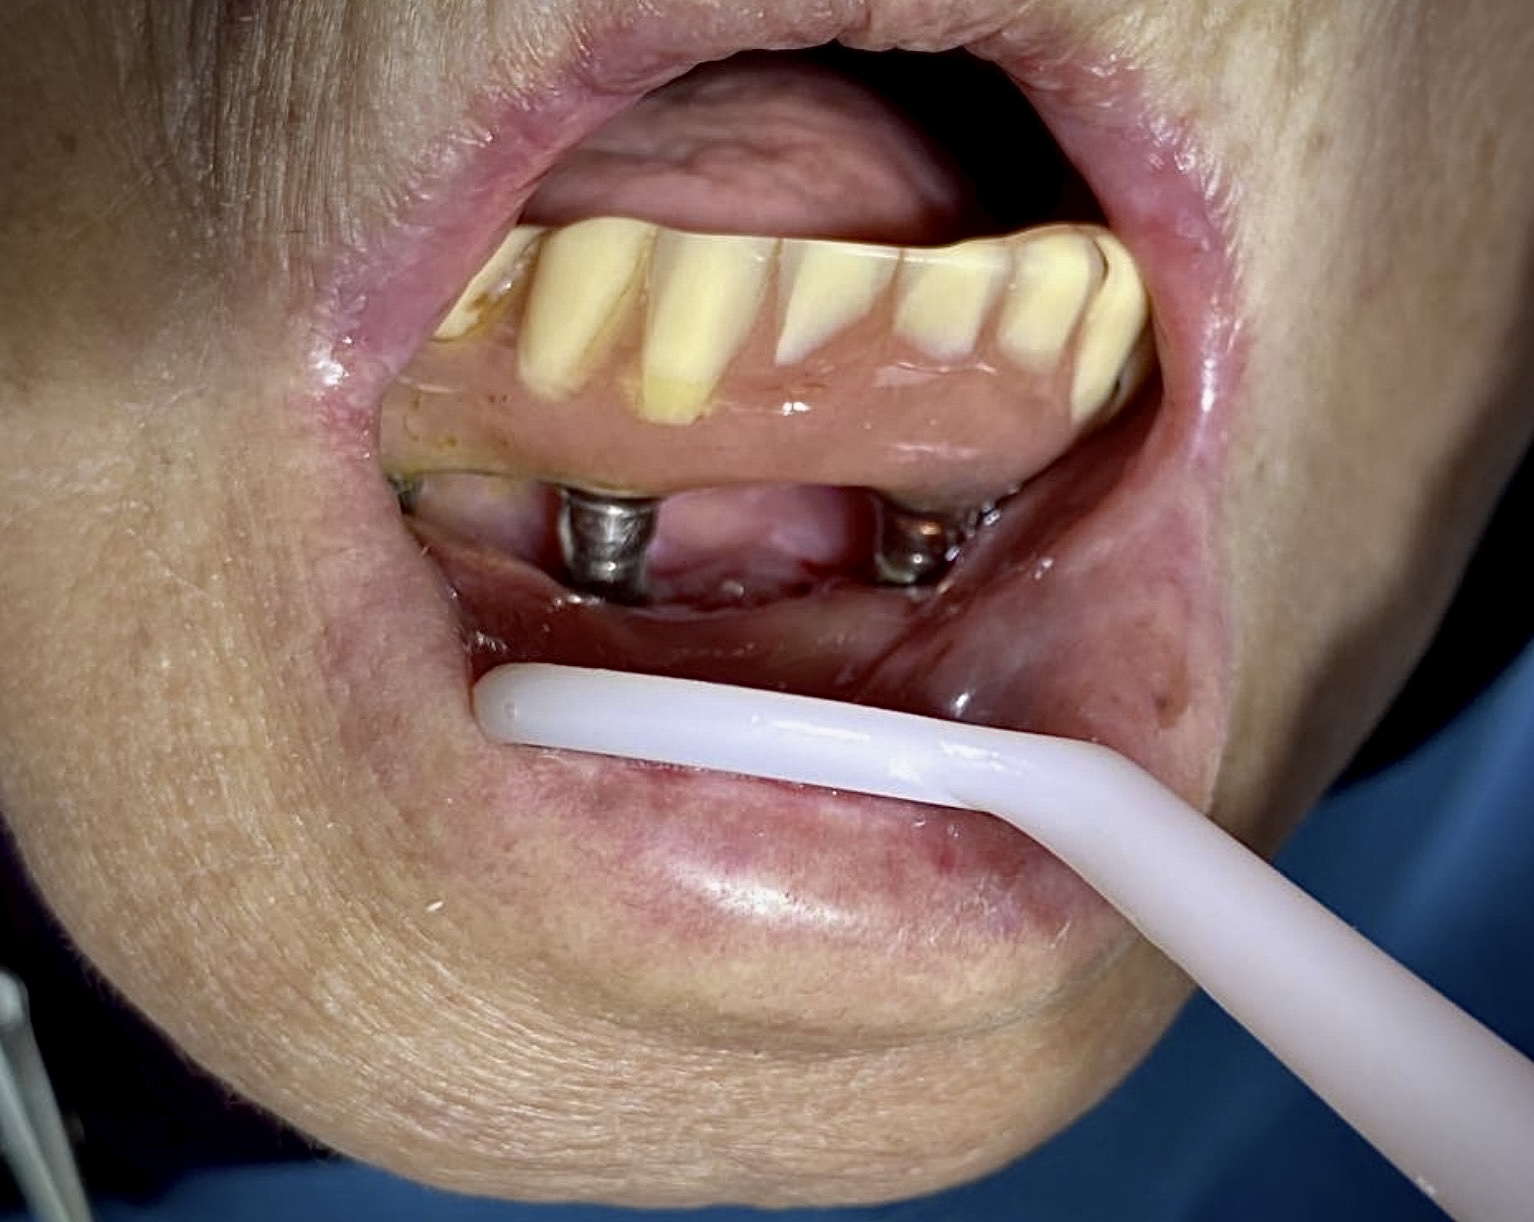

圖1 – 植體周圍炎牙齦組織已破壞、萎縮嚴重,植體螺紋已明顯裸露將近一半,導致 All on 4失敗⋯

患者在他院進行下顎All on 4(5)治療,隨著使用時間的推移累積,漸漸感覺飲食上假牙的不適,反覆有牙齦紅腫發炎的狀況⋯

於是選擇前來本院檢查進行治療,經由謝政言醫師檢查發現其假牙材質為樹脂,而非目前普遍採用的全瓷(鋯)假牙,樹脂表面比自然牙更容易附著牙菌斑,加上患者沒有定期回診清潔,居家清潔也不夠徹底,堆積厚厚的牙菌斑,牙結石也快速積聚⋯

圖2 – 植體周圍堆積厚厚的牙結石,周圍組織已發炎流失

而假牙錯誤不良的咬合設計,導致磨耗不均,假牙螺絲容易鬆脫,影響咀嚼效率,植體周圍炎也已有明顯的破壞程度,植體螺紋已經裸露將近一半,導致All on 4失敗⋯